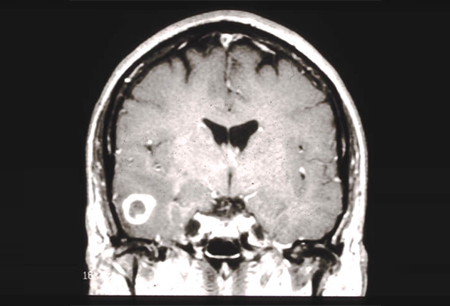

The original duke university hospital, first known as the duke clinic, opened in 1930 with a grant from james b. Preston robert tisch brain tumor center. With more brain tumor procedures performed than almost any other program in texas, we offer the treatment for brain tumors.